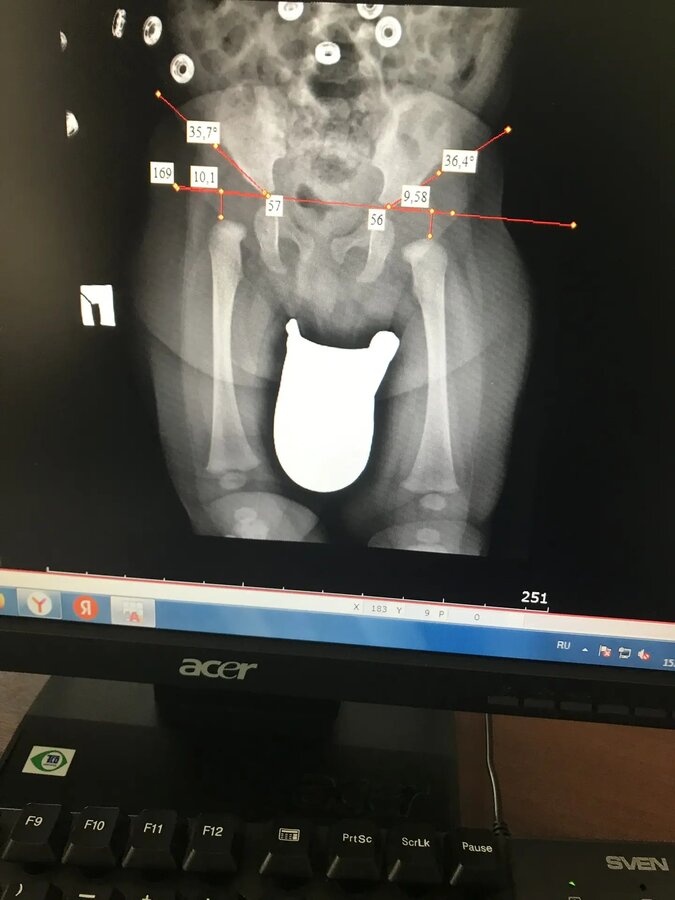

Дмитрий Олегович,здраствуйте, в 3,5 месяца после рентгена поставили диагноз дисплазия ТБС, прописали стремена Павлика,стоит ли ещё что то добавить к лечению?насколько все плохо,есть ли шанс ,что данный метод поможет,физио проходили ещё и 1,5 месяца,там делали УЗИ, были небольшие отклонения от нормы,ничего кроме массажа и физио не прописали,все рекомендации выполняли,сейчас 4 месяца нам

Дмитрий Олегович,здраствуйте, в 3,5 месяца после рентгена поставили диагноз дисплазия ТБС, прописали стремена Павлика,стоит ли ещё что то добавить к лечению?насколько все плохо,есть ли шанс ,что данный метод поможет,физио проходили ещё и 1,5 месяца,там делали УЗИ, были небольшие отклонения от нормы,ничего кроме массажа и физио не прописали,все рекомендации выполняли,сейчас 4 месяца нам 4 месяца